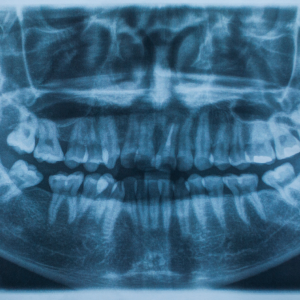

The X-ray process was swift and seamless. Using the latest technology, the clinic provided a detailed image of Rani's dental structure, revealing an impacted wisdom tooth – the culprit behind her discomfort. For Rani, this revelation was a turning point. The mystery was solved, and with it, a weight was lifted off her shoulders. She now had a clear path forward, guided by Dr. Arjun’s expert advice.